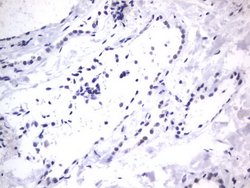

RBFOX1 Mouse anti-Human, Clone: OTI4F9, lyophilized, TrueMAB™

| Immunohistochemistry (Paraffin), Western Blot | |